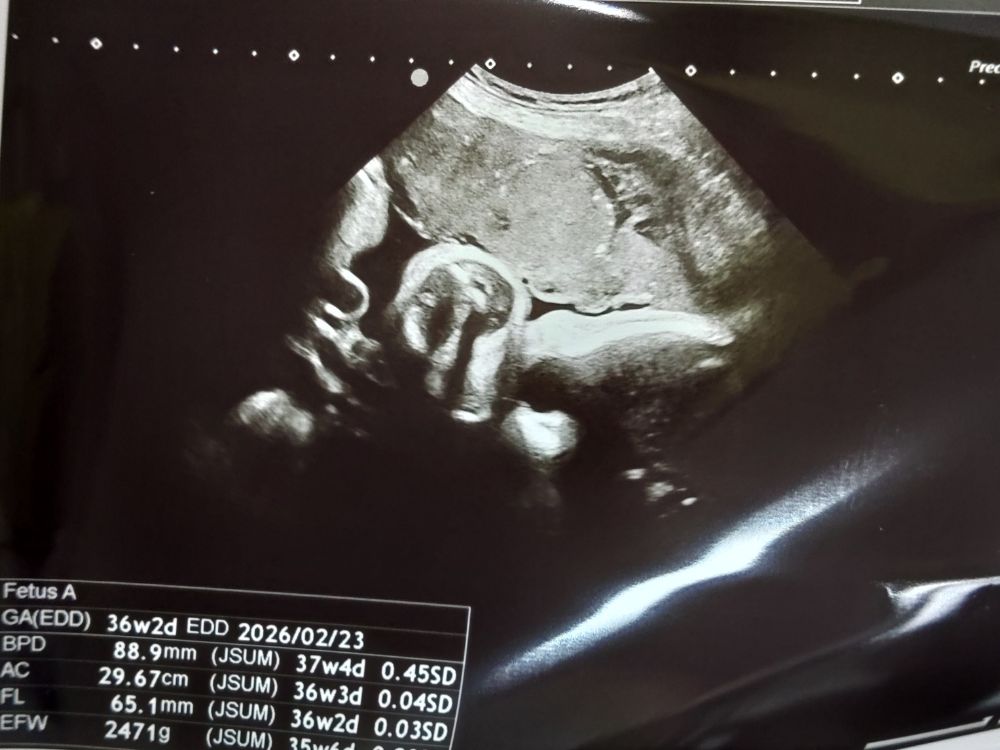

医師の診察|胎児体重は約2,471g

超音波での確認の結果、

- 胎児体重は約2,471g

とのことでした。

2週間前(34週の妊婦健診:約2,336g)から、

+100gほど増えていて週数の平均で順調とのことでした。